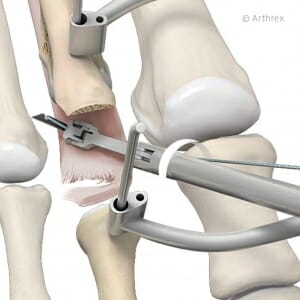

Durch 2 mm Minischnitte wird der Mittelfußknochen mit der Fräse durchtrennt und damit verkürzt.

Zugang zur Zehenbasis von plantar; mit der Fräse werden mindestens 2 mm entfernt und somit wird der Zeh verkürzt.

In den vergangenen fünf Jahren haben wir die minimal-invasive Korrektur der Hammerzehen zunehmend mit gutem Erfolg eingesetzt. Bei diesen minimal-invasiven Hammerzehenkorrekturen werden in der Regel die Gelenke nicht reseziert – man nimmt nur eine Lösung der Gelenke durch kleine 2 mm messende Hautschnitte vor. Auch werden die kurzen und die langen Beugesehnen und die Strecksehnen der Zehen durchtrennt. Diese Sehnenenden wachsen dann in Verlängerung wieder zusammen.

An der Basis des Zehs wird von der Fußsohle her durch einen 2 mm Schnitt eine Fräse eingebracht, der Knochen durchtrennt und verkürzt. Die Verkürzung des Zehs um 2 mm, teilweise auch bis zu 10 mm, ist bei entsprechend langen Zehen und zur Entspannung der Weichteile angezeigt, um die Zehen wieder auszurichten.